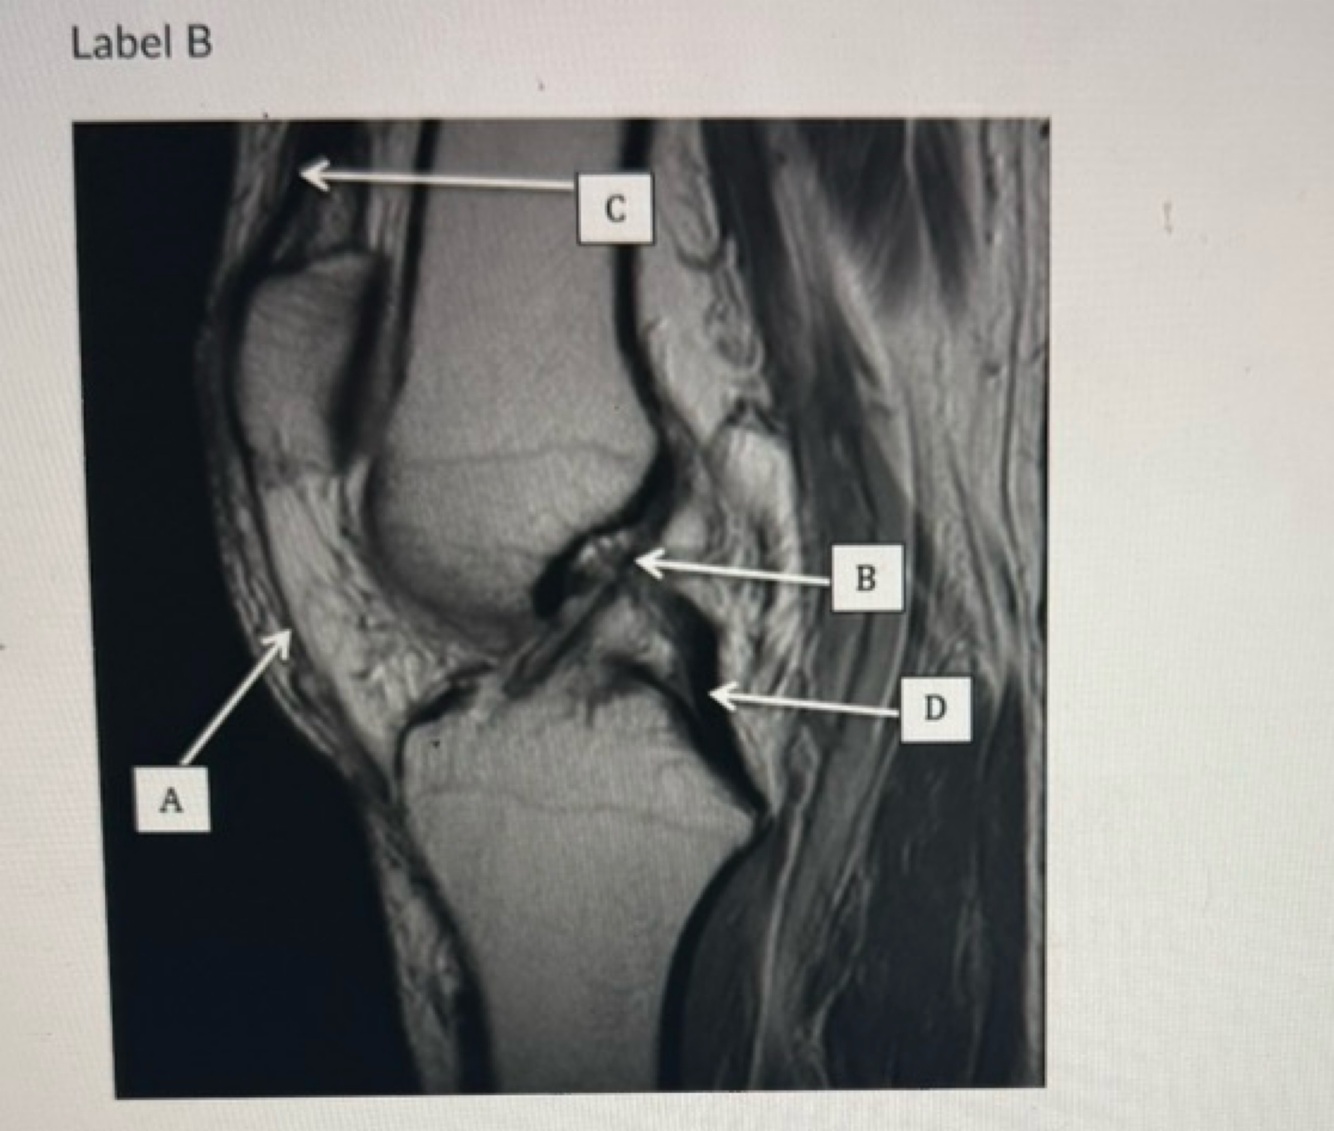

14

Q

A

B